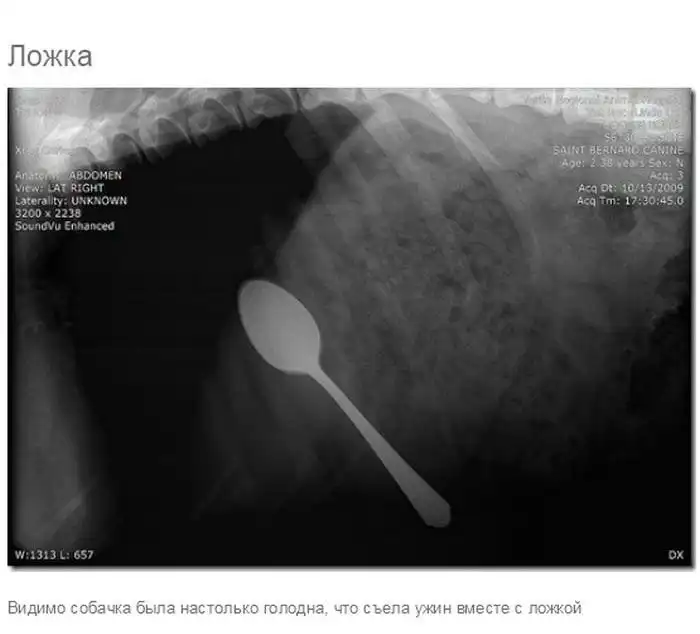

Что может оказаться в желудке собаки

Думаю, всем собачникам известно, что порой у собак бывают такие заскоки, когда они в прямом смысле слова жрут все подряд.